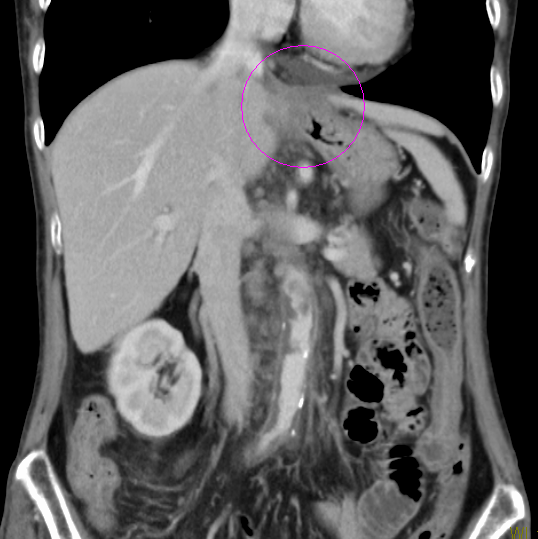

化学療法のみでの根治は難しく、次にあげる目的で実施されます。

- 術前化学療法:手術でがんが取り切れる可能性を高める、微細な転移がんの縮小などを目的として行われる場合があります

術前化学療法の例(造影CT画像)

治療前

治療後